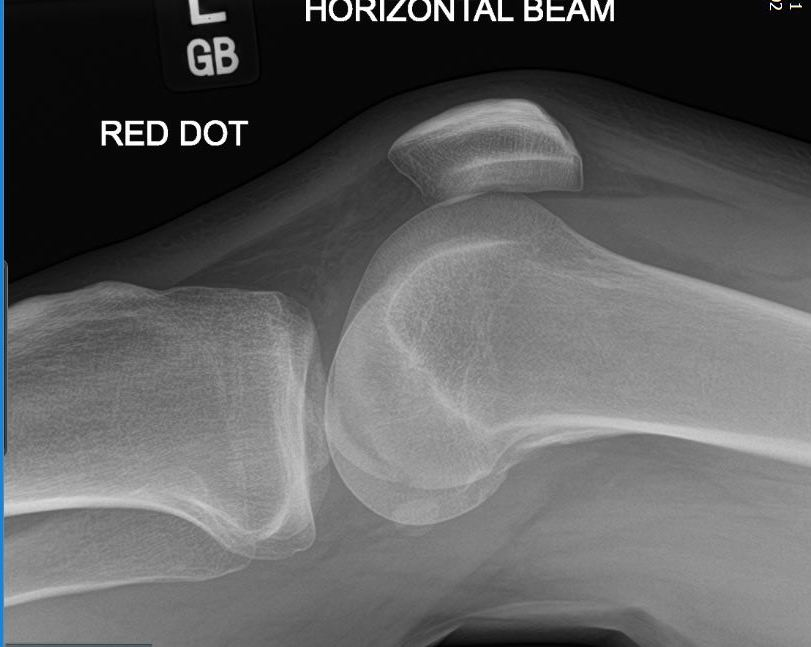

A healthy 37-year-old man sustained a knee injury after performing a deep flexion maneuver while playing a virtual reality game, with a VR headset on. His patella had dislocated laterally after he fell onto his knee whilst in deep flexion. There was no previous history of patella instability. On physical examination, the patient had a body mass index (BMI) of 33 and no signs of compartment syndrome. The patella was dislocated laterally, the knee was swollen, and tender over lateral distal femur. Radiographs of the left knee revealed a lipo-hemarthrosis and a large OCF of the lateral condyle of the femur (Figure 1 & 2). The patella was reduced in the emergency department and on repeat examination there was exquisite tenderness over proximal medial border of the patella in the area of the medial patella-femoral ligament (MPFL) attachment. Further tenderness was elicited over the lateral joint line. The patient was unable to straight leg raise and could hardly flex the knee to 30 degrees. The leg was placed in an extension splint and the patient was allowed non-weight-bearing on crutches.

Figure 2 Lateral Radiograph Knee showing lateral femoral condylar osteochondral fracture.